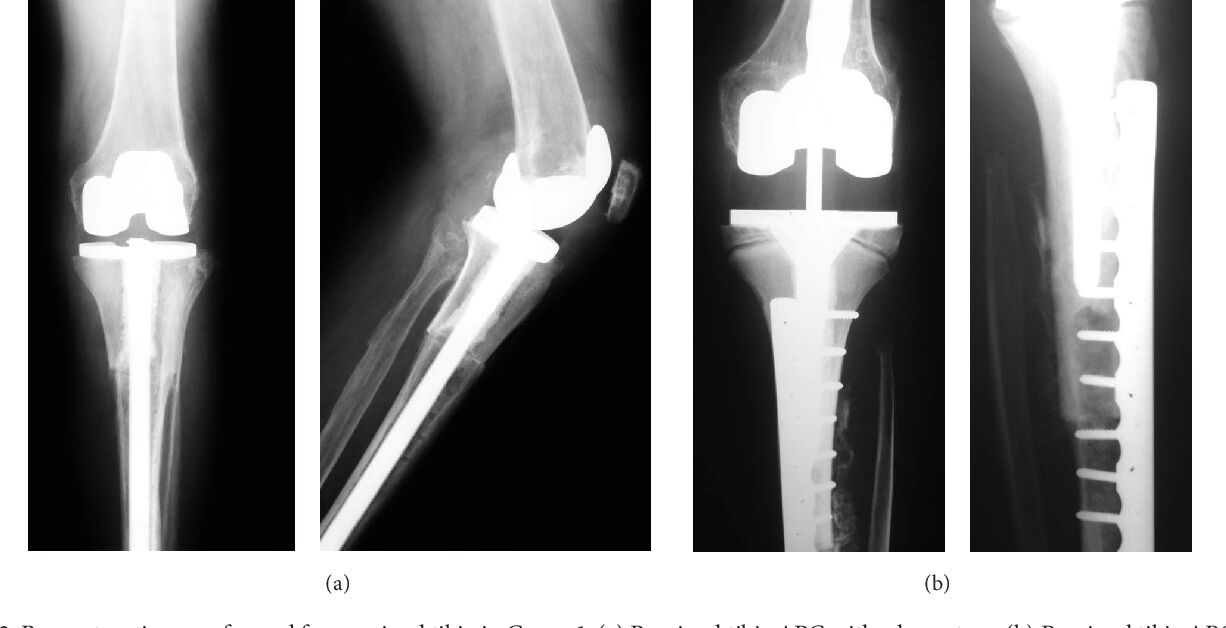

(a) semi constrained

(b)fully constrained